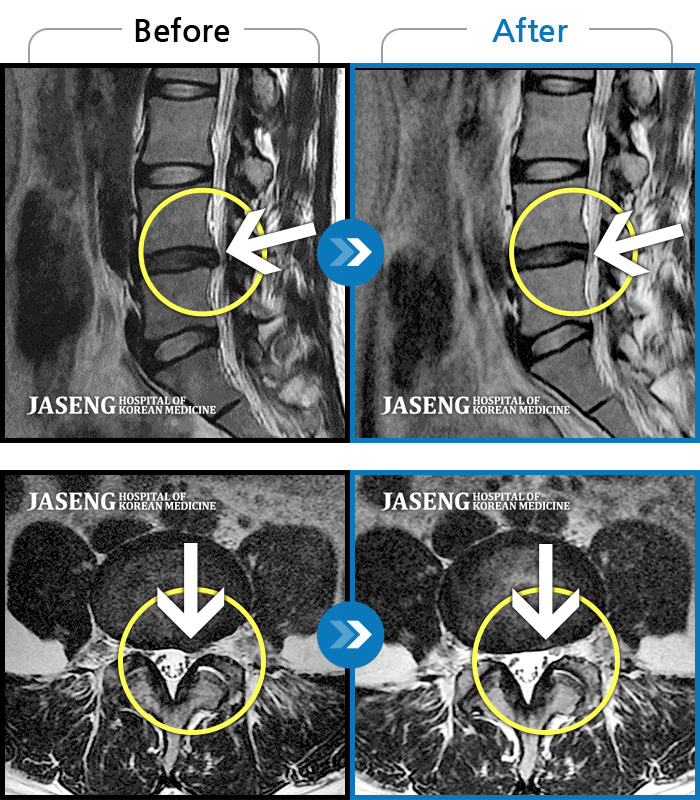

Before

After

환자에게 사전 동의를 받아 동일 조건에서 촬영되었습니다.

개인에 따라 치료 후 부작용이 발생할 수 있으니 의료진과 상담 후 치료를 진행하시기 바랍니다.

처음 내원 시 좌측 엉덩이가 많이 아프고, 좌측 다리로 저림이 심하며 특히 좌위시 하지 방사통이 심하여 1분도 좌위가 어려워 식사도 서서 하는 등 정상적인 활동이 힘든 상태였습니다.

좌측 승모근부터 견갑골까지 이어지는 통증, 좌측 상완 비증으로 내원하셨습니다.